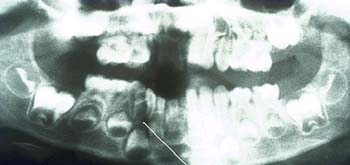

La evidencia clínica de una enfermedad periodontal grave fue respaldada por las pruebas radiográficas en las que se observa una pérdida de hueso de más del 70% en los incisivos mandibulares y la presencia de un grado de movilidad 2 para los cuatro incisivos.

Las radiografías de la férula acabada verifican la unión de los incisivos con periodontitis.

Desde un punto de vista incisal la férula tiene un volumen mínimo. Las radiografías de la férula acabada verifican la unión de los incisivos con periodontitis. La radiografía muestra como la fibra está incrustada en el composite.